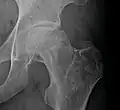

Radiography of avascular necrosis of left femoral head. Man of 45 years with AIDS.

Nuclear magnetic resonance of avascular necrosis of left femoral head. Man of 45 years with AIDS.